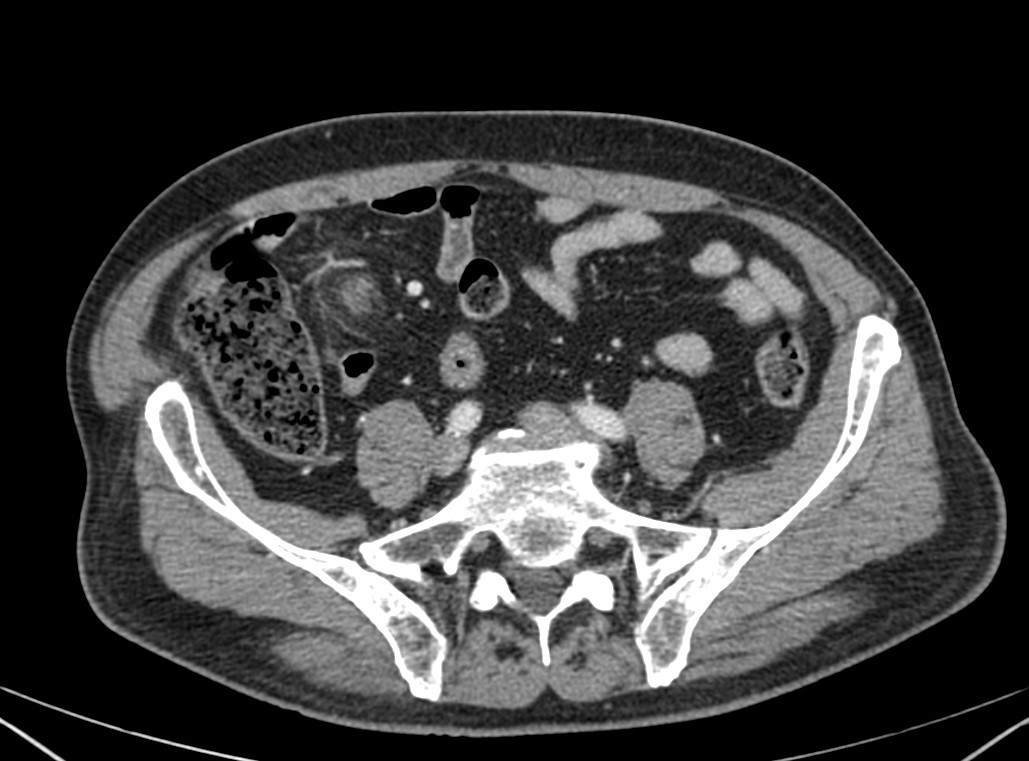

Ante la persistencia del dolor, el elevado IMC del paciente y la necesidad de descartar patología de FID, apendicitis, se decidió realizar TAC de abdomen:

Nos enfrentamos a un poceso que afecta el Epiplon, más concramente un apéndice (o colgajo) del mismo, compuesto por grasa y vasos que se inflaman por compromiso vascular venoso. Se denomina Apendagitis y lo podemos confudir, entre otras entidades, con una apendicitis.

TAC: Imagen oval con aumento de la atenuación central, inferior a 5 cm de diámetro, contigüa al colon, con afectación de la grasa periférica. El aumento de la atenuación central es un signo de trombosis venosa muy útil para el diagnóstico, pero su ausencia no excluye en diagnóstico de apendagitis. Otros hallazgos, como aumento de la pared colónica o formación de abscesos son raros. Aunque los síntomas remiten en dos semanas, los cambios en la TAC pueden prolongarse más tiempo (pueden mantenerse, disminuir o quedar una atenuación residual), aunque en 6 mese suele haber remitido completamente. En Ecografía suele observarse en el área de máxima sensibilidad al dolor, una masa hiperecogénica, inferior a 5 cm, no compresible, adyacente al colon y sin señal Doppler.